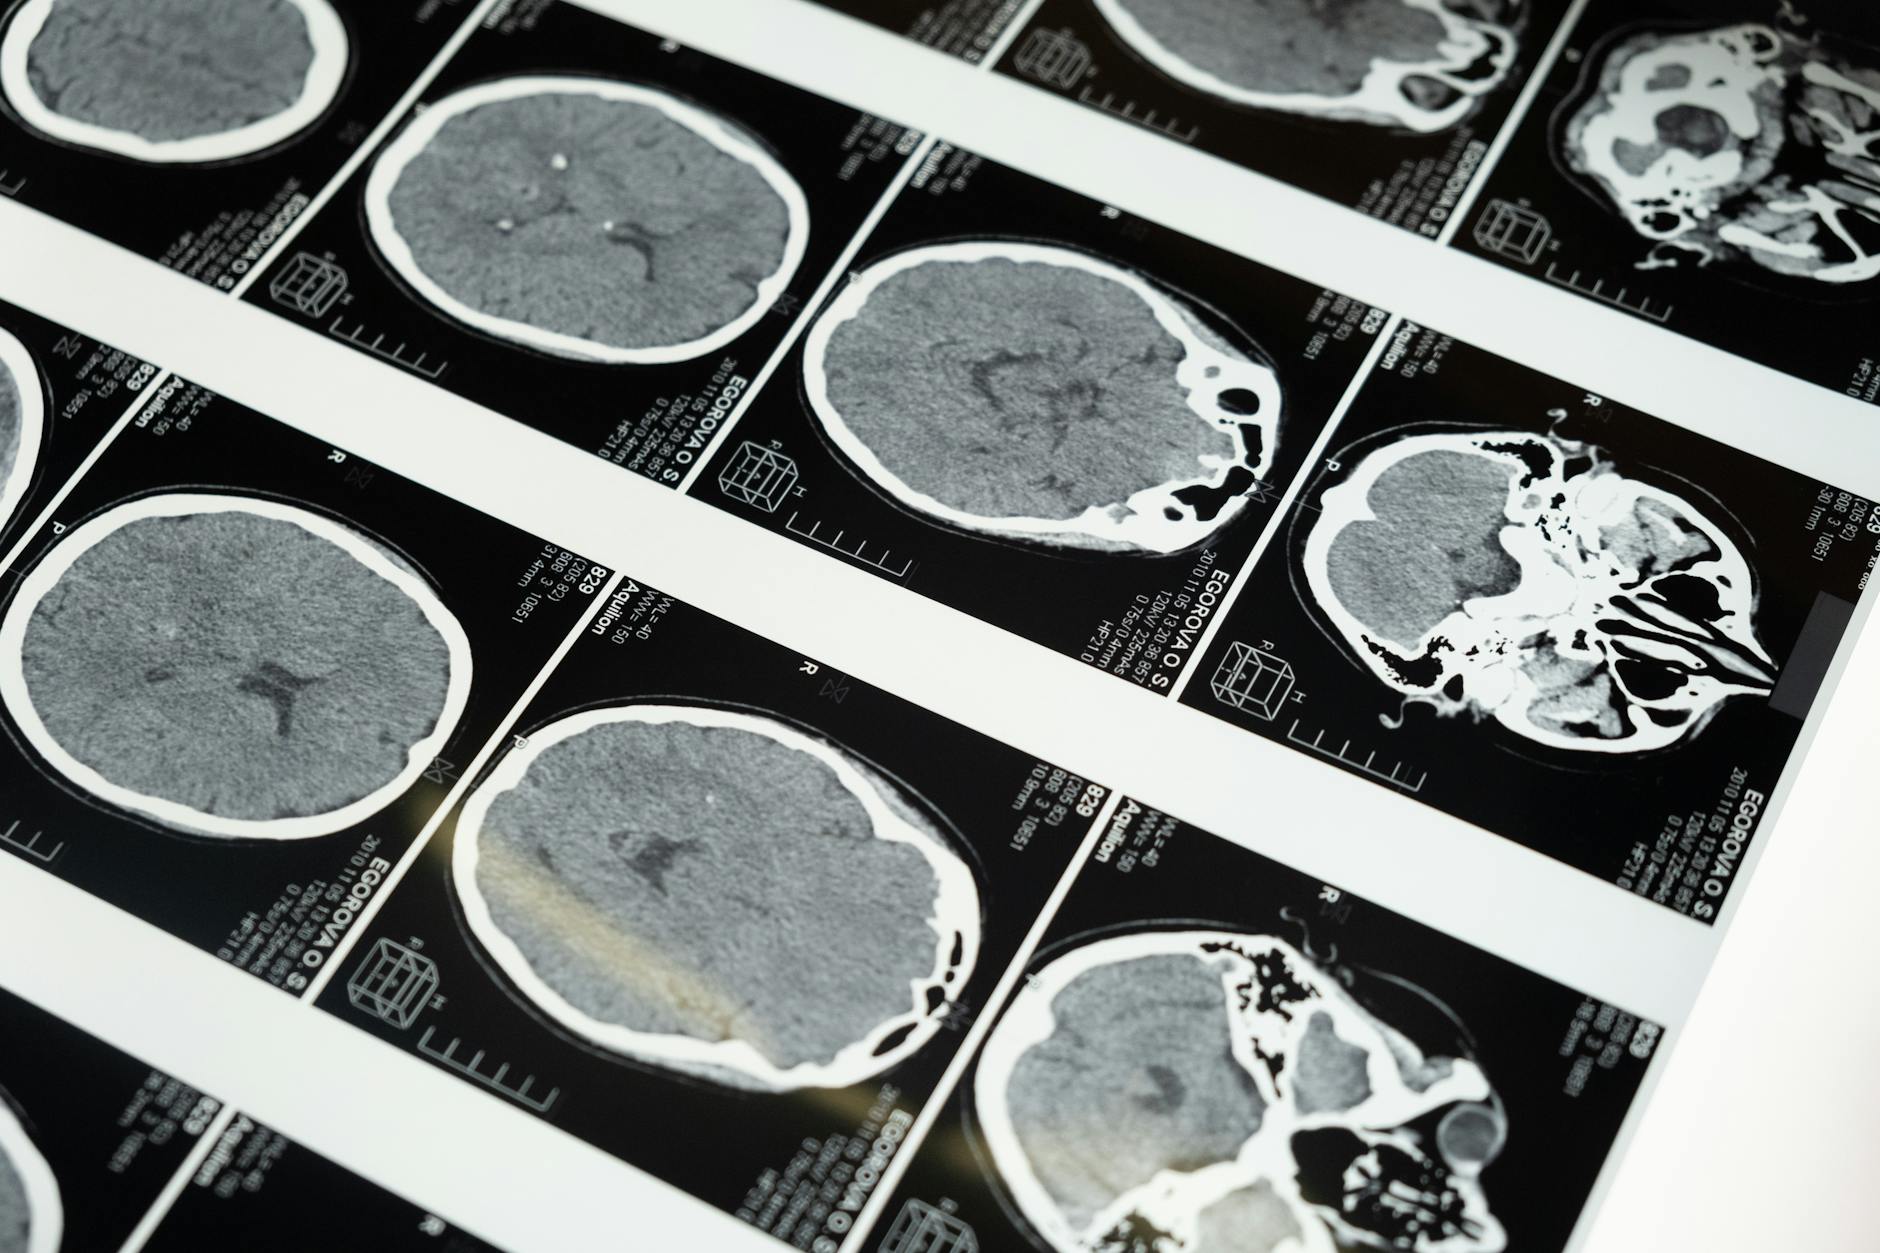

Los infartos, los derrames cerebrales y otras enfermedades cardiovasculares suponen el 41,17 % de las muertes en accidentes de trabajo, según datos del Ministerio de Trabajo y Economía Social de España.

De acuerdo con las cifras oficiales, se ha presentado un aumento del 8,6 % de fallecimientos por causas «estrictamente naturales» hasta llegar a las 266 defunciones durante la jornada laboral.

A estas causas le siguen «de lejos» los atrapamientos, los aplastamientos y las amputaciones (15,32 %), los accidentes de tráfico (14,86 %) y los golpes como resultado de caídas (14,55 %).

Representantes del Instituto Nacional de Seguridad y Salud en el Trabajo y la Fundación Española del Corazón destacaron la necesidad de que las empresas impulsen una «cultura de cardioseguridad», con motivo del Día Europeo de la Prevención del Riesgo Cardiovascular.

Todo ello pasa por realizar una valoración «adecuada» del riesgo cardiovascular en las empresas, así como establecer programas de prevención y promoción de la salud cardiovascular en el entorno laboral.